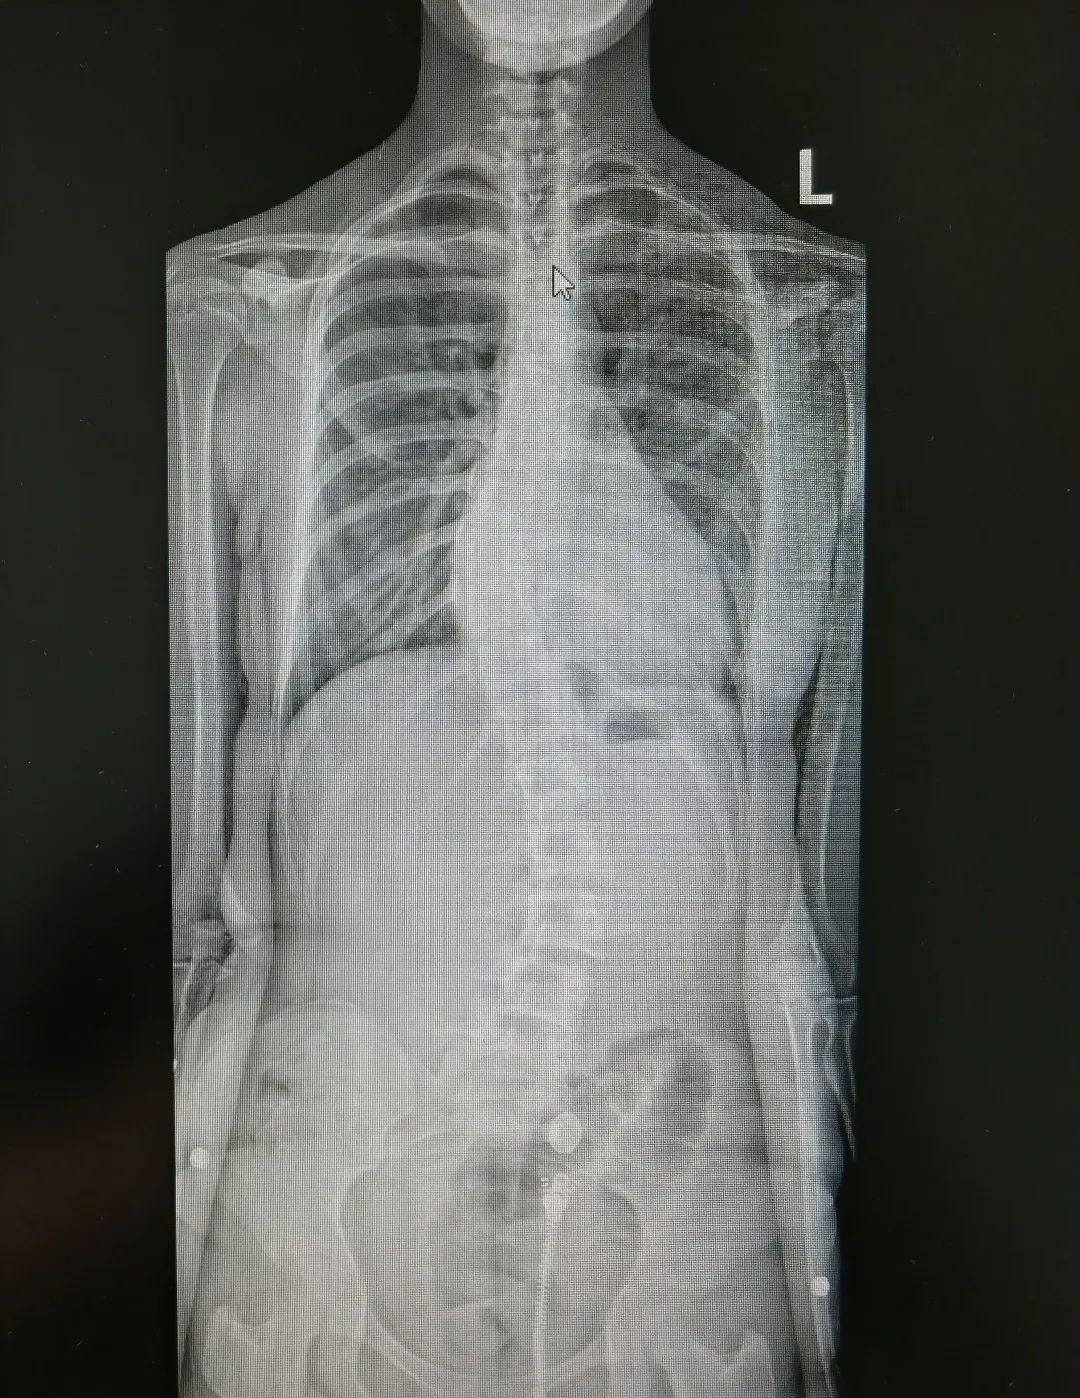

青少年特发性脊柱侧弯术前术后图

“在所有脊柱侧弯类型中,临床中占比最高、最常见的就是青少年特发性脊柱侧弯,约占脊柱侧弯的百分之70%。目前它的发病原因尚不清楚,可能与遗传、免疫、激素、姿势不良等因素有关,往往从10岁左右开始发病。根据严重程度不同,治疗方案也有差异。部分患儿可以采用支具矫形、物理康复锻炼等方式进行保守治疗,但是如果侧弯度数大于40°,就需要考虑手术矫形。”

陈文昊副主任表示,虽然青少年特发性脊柱侧弯目前病因不明,但部分患有青少年特发性脊柱侧弯的孩子都有一个特点——短时间内长得都比较快。青春期骨骼快速生长发育,原本轻微的脊柱侧弯此时也会迅速进展,一年甚至可长歪10度以上。

他同时提醒家长:如果孩子平时坐姿不良、体态不好,短期内长得又很快,尤其要警惕青少年特发性脊柱侧弯。